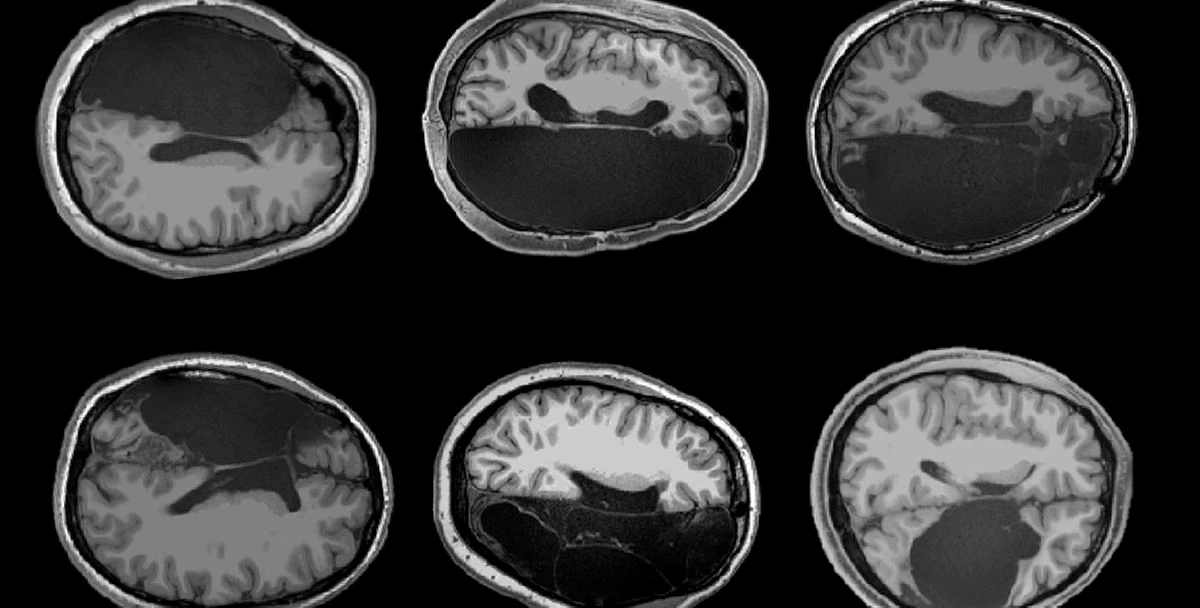

En un artículo reciente publicado en la revista Neuropsychologia se menciona el caso de una mujer que un día, durante un chequeo médico, descubrió que le faltaba el lóbulo temporal izquierdo. Esta región, normalmente, desempeña una función importante en la capacidad para entender lo que se nos dice. Este tipo de ausencia debería suponer algún tipo de limitación en las habilidades lingüísticas de la paciente, pero ella nunca las había experimentado y jamás había intuido que algo faltase en su cerebro.

Casos como este no son tan extraños y en muchas ocasiones tienen que ver con defectos congénitos que producen accidentes cerebrovasculares en las fases tempranas del desarrollo. De hecho, según recogía un artículo en la revista Wired, a la hermana de la paciente analizada en el trabajo publicado en Neuropsychologia le falta el lóbulo temporal derecho. Pero la naturaleza, con esa especial habilidad para adaptarse a las circunstancias, permitió a las dos hermanas tener una vida normal, reorganizando el cableado de su cerebro para colocar las funciones del lenguaje en las partes intactas.

Javier de Felipe, investigador del Instituto Cajal del CSIC, en Madrid, comenta otros casos de personas sorprendidas por sus particularidades cerebrales, como el de un hombre que por un caso de hidrocefalia durante la infancia “tenía agua en el cerebro y la corteza reducida a una pequeña lámina”, y aun así llevaba una vida normal, “o individuos que viven prácticamente sin cerebelo”. Sin embargo, apunta, “esas alteraciones sucedieron en las primeras etapas de la vida, cuando es posible que gracias a la plasticidad del cerebro, otras regiones intactas suplan las funciones dañadas”. Cuando este tipo de lesiones se producen en edades más avanzadas, el resultado es catastrófico.

En las primeras etapas de su desarrollo, el cerebro humano es mucho más flexible. En esos momentos, “es capaz de adaptarse, de tal manera que, si está afectada la corteza visual, se podría realizar un trasvase para que una parte más dedicada al procesamiento auditivo compense por la otra región perdida”, explica Sandra Jurado, investigadora del Instituto de Neurociencias de Alicante (UMH-CSIC). “Una vez que las conexiones están hechas, cortarlas es traumático, aunque hay casos en los que sí se da una redundancia en el cerebro y algunas conexiones se pueden redirigir para compensar parte de la funcionalidad perdida”, añade.

Jurado recuerda que “existen sistemas de seguridad en el cerebro, como las células gliales que reparan los pequeños daños que se producen en nuestro día a día”, pero también, como en los sistemas de ingeniería de los aviones, que son redundantes para evitar un desastre en caso de que falle una pieza, parece haber partes del cerebro redundantes que se pueden reutilizar en caso de lesión, principalmente durante el desarrollo embrionario o la primera infancia. Esto, además, sucede en las partes relacionadas con la corteza cerebral, la más humana del cerebro. Las partes más primitivas, relacionadas con funciones básicas como respirar o tener hambre, parecen más intocables, pero se puede vivir pese a la falta de grandes partes de la corteza.